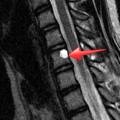

DevamıOp. Dr. Tamer Tekin wrote a new post, Omurga tümörlerinde uygulanan cerrahi tedavi teknikleri 8 yıl 5 ay önce

Omurga tümörlerinde uygulanan cerrahi tedavi teknikleriKemikler, kanserler arasında 3. sırada sıklıkla metastazın olduğu dokulardır. Omurga ise en sık kemik metastazı olan bölgedir. Akciğer, prostat, meme, böbrek, tiroid ve gastrointestinal sistemin primer kanserlerine sekonder olarak omurgaya metastaz gözlenir.